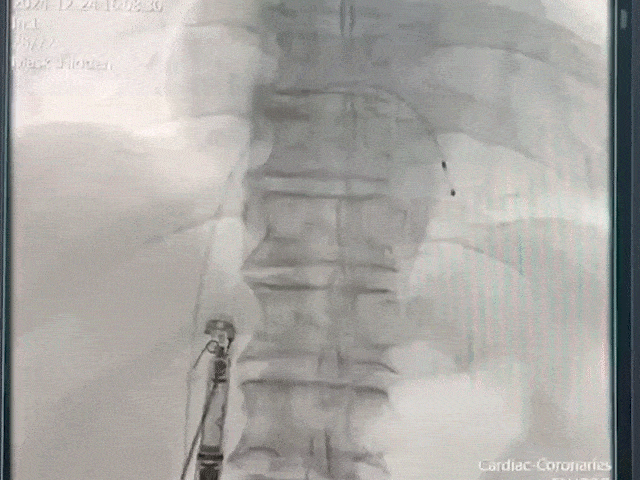

手术过程部分展示

将保护套筒送至下腔心房交界处

后撤保护套筒激活无导线起搏器,调至备用起搏模式

调弯跨三尖瓣进入右室低位间隔

轻微释放调弯精确调整位置